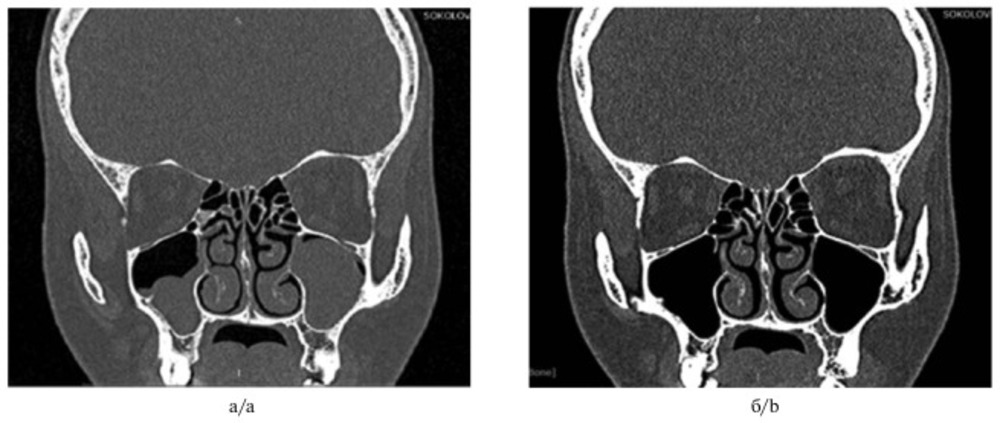

Период отдаленного наблюдения на сегодняшний день составляет от 4 до 14 мес. Все пациенты были выписаны из стационара на 2-е сутки. По данным КТ ОНП (рис. 2)